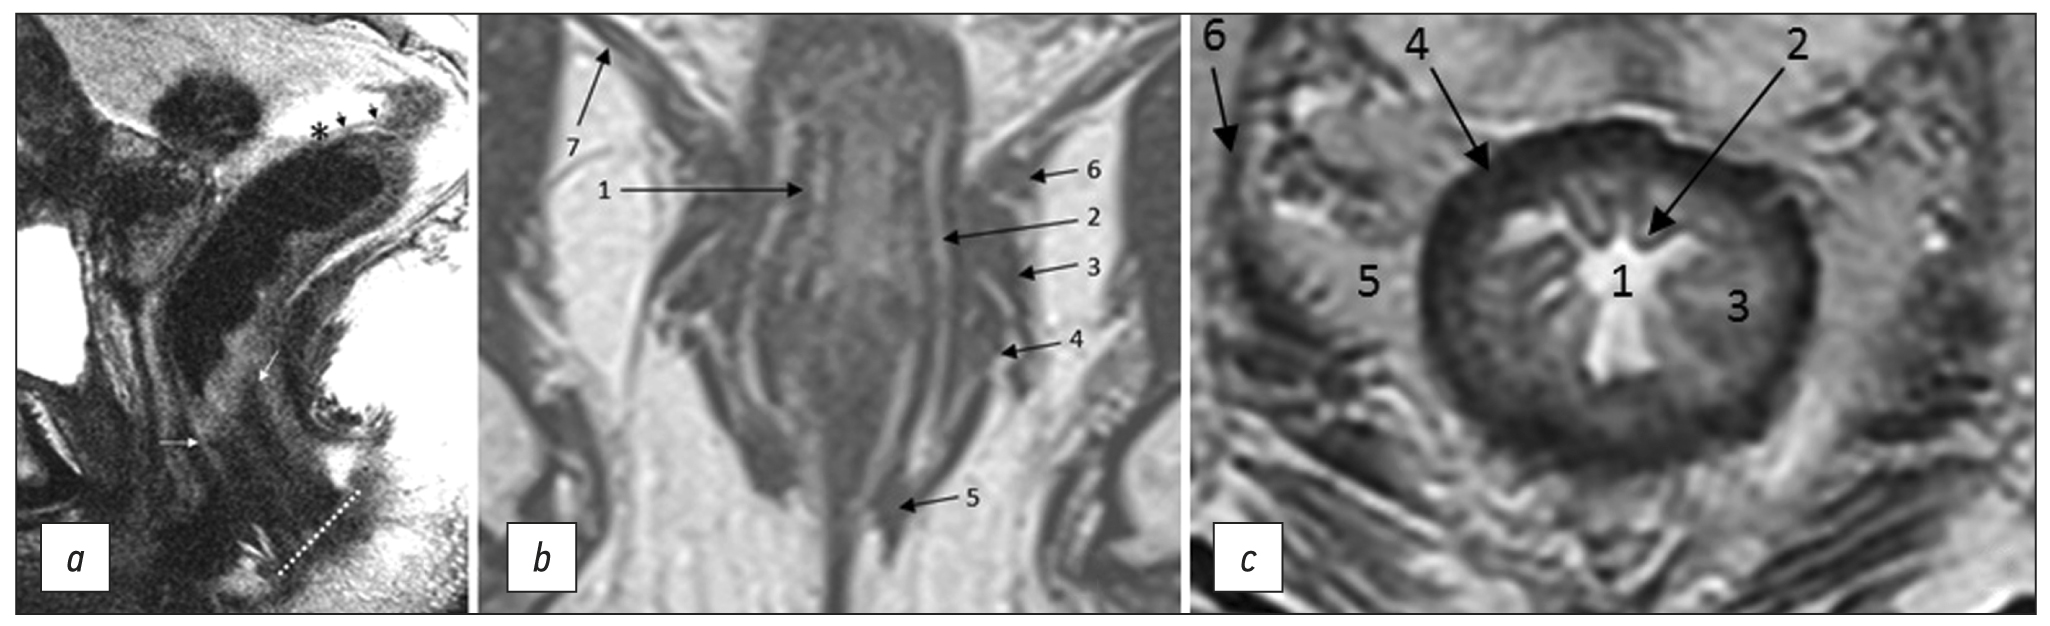

Fig. 1. MRI anatomy of the rectum on T2-WI. (a) Sagittal plane: anal edge (intersphincteric groove; dotted line); anorectal junction (angle) at the level of the upper border of the internal sphincter of the anal canal (white arrows); transitional fold of the peritoneum at the lower point of attachment of the pelvic visceral peritoneum to the rectal wall (asterisk); peritonealized part of the rectum (black arrows). (b) Coronal plane: 1, internal sphincter of the anal canal; 2, intersphincteric space; 3, deep portion of the external sphincter; 4, superficial portion of the external sphincter; 5, subcutaneous portion of the external sphincter; 6, puborectalis muscle; 7, elevator muscle of anus (levator ani). (c) Axial plane: 1, intestinal lumen; 2, mucous membrane; 3, submucosal layer; 4, muscle layer; 5, mesorectal tissue; 6 mesorectal fascia.

Not all lymph nodes located in the pelvis are regional for rectal cancer and are classified as “N.” When assessing pelvic lymph nodes as regional, it is important to consider their location (Fig. 4) and, if possible, indicate it in the examination report. Here are terms related to location, staging, and criteria for lymph node involvement.

The lateral pelvic lymph nodes, situated at the side pelvic walls, are lymph nodes external to the mesorectal fascia, including the external, internal iliac, and obturator lymph nodes. When describing them, it is better, whenever possible, to indicate a more specific location. During primary staging, it is recommended to consider regional lateral pelvic lymph nodes (internal iliac and obturator) with a short axis (≥7 mm) as suspicious [12, 27]. Morphological criteria for lateral pelvic lymph nodes are not recommended [13].

The internal iliac lymph nodes are regional and, in the case of rectal cancer, are included in the scope of dissection of the lateral pelvic lymph nodes. They are located along the internal iliac vessels. At the level of the obturator muscle, they are localized medially to the internal iliac artery; lymph nodes lateral to the internal iliac artery are considered obturator lymph nodes (Fig. 4).

Fig. 4. Localization of the lateral pelvic lymph nodes (colored): external iliac lymph nodes are red; obturator lymph nodes are blue; and internal iliac lymph nodes are green. Shown in levels (a) proximal and (b) distal. EIA: external iliac artery; EIV: external iliac vein; IIV: internal iliac vein; IIA: internal iliac artery; Obt a/v/n: obturator artery/vein/nerve; OIM: obturator internus muscle.

The obturator lymph nodes are regional. They are located between the external and internal iliac arteries, medially to the internal obturator muscle and laterally to the internal iliac artery (Fig. 4).

The external iliac lymph nodes are not regional. They are located along the external iliac vessels (Fig. 4) and are divided into lateral, middle/median, and medial chains. The lateral subgroup is located laterally to the external iliac artery. The middle/median group is between the artery and the vein. The medial group is posterior to the external iliac vein. The lymph nodes in the medial subgroup are located near the obturator vessels and obturator lymph nodes. This can cause diagnostic difficulties because they are often indistinguishable from the obturator lymph nodes localized along the obturator artery at the point of its origin from the internal iliac (hypogastric) artery at the level of the internal obturator muscles [3]. Involvement of the external iliac lymph nodes in rectal cancer is extremely rare. Non-regional lymph nodes are considered suspicious if they measure >10 mm in short axis.

Inguinal lymph nodes are not regional in rectal cancer, but are regional in squamous cell carcinoma of the anal canal. They are located in the groin area below the inguinal ligament. They can be classified as regional for tumors extending below the dentate line [13]. They are divided into superficial (anterior to the saphenous vein and superficial femoral vessels) and deep (medial to the femoral vessels).